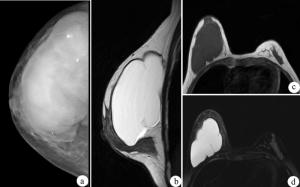

2.鉬靶X線攝片

囊腫大多呈圓形、橢圓形透亮區,多位於乳暈區以外,靠近乳腺的邊緣部位。

3.B超檢查

在乳腺的反射波內,相當於囊腫的部位,出現典型的、邊界清楚的液性平段或液性暗區,液平前後有明顯的進出囊壁反射。通過囊腫中心的縱切和橫切聲像圖,可測定囊腫的3個徑線,了解囊腫的大小和範圍。兩囊壁反射間的距離,即代表囊腫的前後徑。